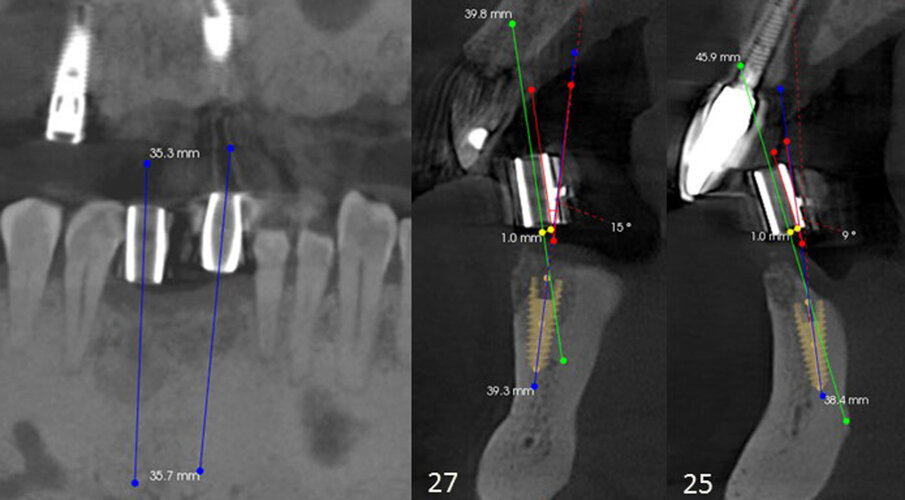

A virtual implant was placed at each site in the software. It was determined that, based on the trajectory of the guide sleeves, that both implant sites were angled to the facial aspect. This would create lingual perforation when the osteotomies were prepared, and a correction would be necessary with the surgical guide that would be fabricated. Additionally, both planned implants would need to be shifted and angled lingually to allow the definitive restoration to have lingual access openings for the abutment screws. Analysis determined that the implant at the central incisor would need to be angled 9° to the lingual aspect and offset to the facial aspect at the crest by 1 mm and the canine angled 15° to the lingual aspect and offset to the facial aspect by 1 mm (Figs. 5a–c).

Figs. 5a–c: CBCT views showing orientation of the diagnostic guide sleeves in relation to the bone present (green line), indicating correction required on both planned sites to have implants placed within the arch. The red line indicates the angle correction, and the yellow line indicates the offset measurement to the facial and lingual aspects. The blue line indicates the newly planned axis of the implant.